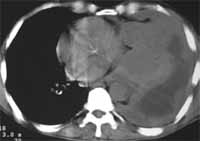

Figura 4. Adenocarcinoma basal derecho.

Los hallazgos clínicos no difieren de un síndrome constitucional, con fiebre, astenia, adinamia. Sin embargo, dado su componente tumoral tiene una mayor incidencia de complicaciones trombóticas, que los otros tipos de tumor (17-19).

Figura 5. Adenocarcinoma de hemitórax izquierdo con compromiso pleural y derrame pleural asociado.

Su pronóstico está directamente relacionado al estadio en el que se encuentre. Situación que será revisada más adelante, teniendo sobrevivas tan disímiles en los estadios I del 90% a los cinco años hasta del 55% en los estadios IIIB en adelante (17-19).